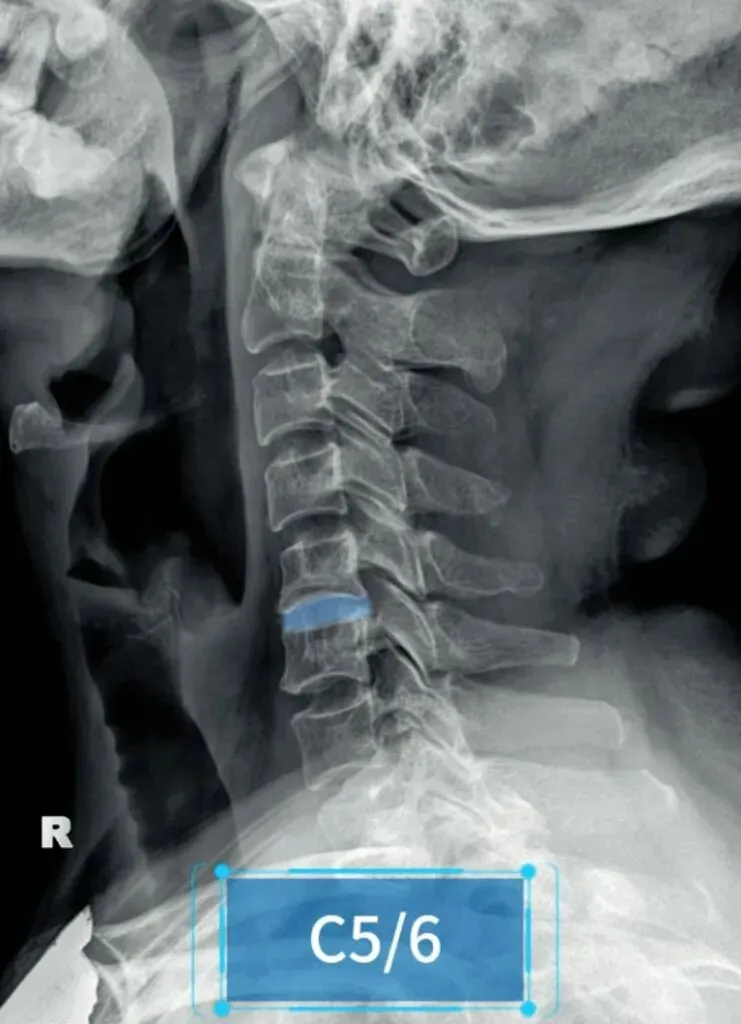

五间是指颈椎椎间隙的变化,主要在颈椎侧位片上观察椎间隙变化同时也反映了椎间盘的变化。

颈椎的退变最早发生在C56椎间盘上,因此C56椎间隙也最早发现变窄的征象。

颈椎骨性椎体为前低后高,

而椎间盘则为前高后低,因此颈椎的生理性前凸是由椎间盘的前高后低所形成的。

在正常情况下,C23、C34和C45间隙大致相等,椎间隙前部为3.8毫米正负0.5毫米,

后缘间隙为1.9毫米正负0.28毫米。

C56间隙较上为宽,而C67间隙最宽,但C7与T1间隙又较窄。